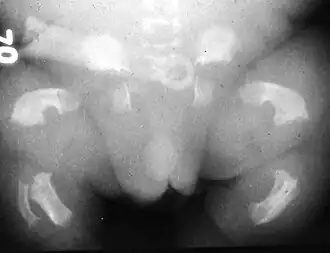

- Chondrodysplasies : maladies osseuses constitutionnelles génotypiques, héréditaires, liées essentiellement à des troubles du développement des cartilages de conjugaison des os longs et des vertèbres.